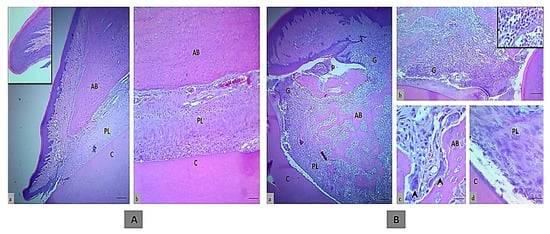

The histology of an incisor tooth and periodontal tissues of rats in the control negative group sacrificed after one month, comprising gingival tissue, periodontal ligament, and alveolar bone, displayed normal structures and arrangement without any indication of inflammation or bone loss (Figure 1A).

Meanwhile, the main histologic feature of the periodontal tissue of rats in the control positive group showed severe damage of the periodontal tissue in comparison to the rats in the control negative group. This damage included disruption of the gingival epithelial lining tissue that led to pocket formation and severe infiltration into the insertion point of inflammatory cells such as neutrophil and mononuclear cells (macrophages, plasma cells, and lymphocytes) that were found in gingival epithelial tissue, periodontal ligament and alveolar bone, even in granulation tissue in the crest, and also in the alveolar bone, as seen in Figure 1B.

Active bone resorption was found along with high numbers of osteoclasts involved in a large bone lacuna resorption (Howship’s lacuna) with ruffled border, marking the irregular bone surface. The newly formed bone trabeculae were disorganized. There was a newly formed layer of osteoid tissue that contained a large number of osteoclast, fibroblast, mononuclear inflammatory cells and dilated blood vessels. The periodontal ligament was partially degenerated and showed disorganized proliferation of periodontal ligament tissue (collagen fibers and fibroblast) that had not attached to the cementum surface.

Figure 1. The histologic section of an incisor tooth and periodontal tissue of rats. (A) The control negative group, a and b. Normal histological and structural organization of the intact gingival lining epithelium and periodontal tissues (inset is normal histological features in low magnification), (H&E, scale bar 10 μm in section a and b). (B) Control positive group, a–c. Marked periodontal pocket (P) with disruption of the junctional epithelium and granulation tissue in the insertion point, also above the bone crest that indicated by G and inset, that showed the higher magnification of inflammatory cells infiltration, disorganized bone trabeculae (BT) and irregular bone surface with a presence of osteoclasts involved in bone matrix cavity (black arrows), d. The wide periodontal ligament space is filled with disorganized fiber and proliferating periodontal ligament tissue that has not attached to the cementum, (H&E, scale bar 10 μm in section a, and 20 μm in section b and 40 μm in section c and d). (AB; alveolar bone, PL; periodontal ligament and C; cementum).